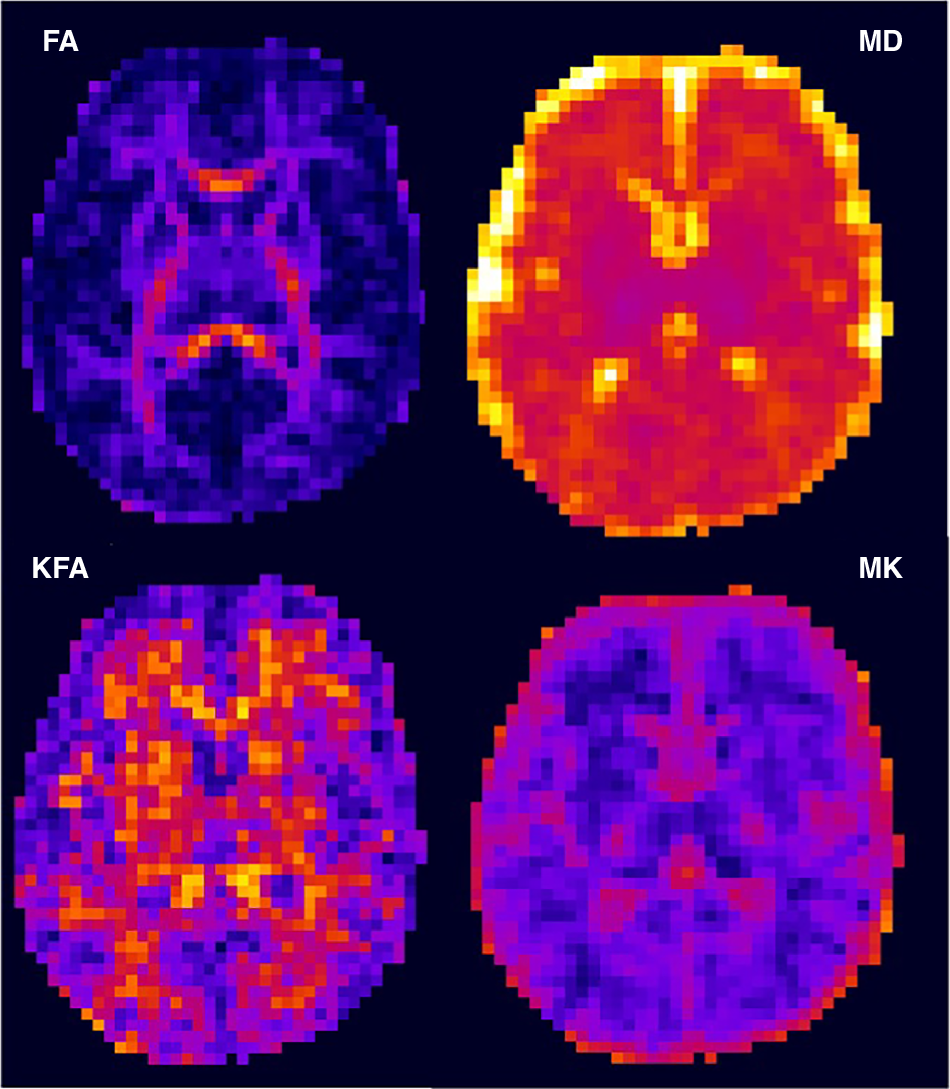

Fig. 2: Diffusivity and kurtosis axial image from a 43-week 1-day GA neonate that had no pathologic findings on the MRI reading.

Top row, conventional diffusivity measures of fractional anisotropy (FA) and mean diffusivity (MD). Bottom row, kurtosis fractional anisotropy (KFA) and mean kurtosis (MK). The diffusivity has units of μm2/ms. While the FA is quite low in most regions (deep purple) except the genu and the splenium of the corpus callosum, the KFA shows higher values (red/yellow) with more diversity in the reported higher-order anisotropy, reflecting tissue complexity. Within the MD map that the thalami (purple voxels) are approaching their asymptotic lowest value, while the MK map shows greater detail in this region. Interestingly, the MK has low values within the WM, with slightly higher values in the cortex and thalamic gray matter. Eventually, during myelination and maturation, the MK in the WM will exceed that in the gray matter due to the restriction from biological barriers, such as myelin.